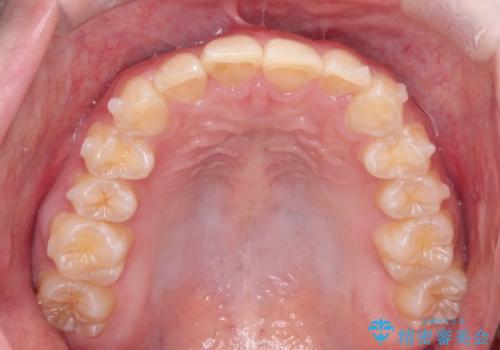

インビザラインで前歯のガタガタをきれいな歯並びへ

- 前歯のガタガタが気になるとのことで来院されました。

上顎の前歯の叢生があったのと、下あごの前歯が通常より1本欠損(先天欠損)していました。

上顎の歯と歯の間をわずかに削りスペースをつくり、並べる計画としました。インビザライン治療を選択されました。

しっかりとインビザラインを使用していただけたので、スムーズに治療を終了させることができました。